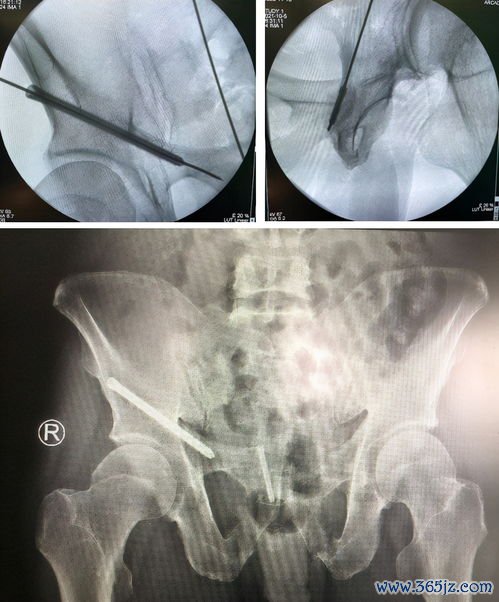

先天性髋关节脱位:髋关节不稳

先天性髋关节脱位:髋关节不稳的机制、表现与临床意义 先天性髋关节脱位(DDH)是儿童骨骼系统最常见的畸形之一,其本质是髋臼与股骨头之间的匹配关系异常,导致关节稳定性丧失。髋关节不稳并非一个孤立的症状,而是连接遗传易感性、宫内环境、产后力学因素与远期功能障碍的核心病理生理环节。深入剖析髋关节不稳,有助于我们更全面地理解DDH,并为临床实践提供清晰的指引。 一、...

DDH:髋关节发育不良

守护髋关节的“成长密码”:认识与应对发育性髋关节发育不良 在儿童骨科门诊中,发育性髋关节发育不良(Developmental Dysplasia of the Hip,简称DDH)是一个并不少见却常被忽视的“成长隐患”。它并非严格意义上的先天性疾病,而是一种在胎儿期或婴幼儿发育过程中逐渐显现的髋关节结构异常。髋关节由髋臼和股骨头构成,正常情况下,股骨头应被髋...